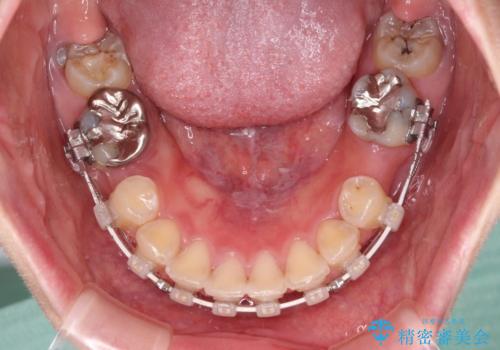

上下顎歯列ともに前方に突出していましたが、上顎歯列がより前方位にあったため、上顎左右は第1小臼歯を、下顎左右は第二小臼歯を抜歯することとしました。

目立たないワイヤー装置にて抜歯矯正を行うこととしました。

下顎は過剰歯が埋伏しており、それが原因となってスペースが閉じなかったため、途中で抜歯して速やかに仕上げました。